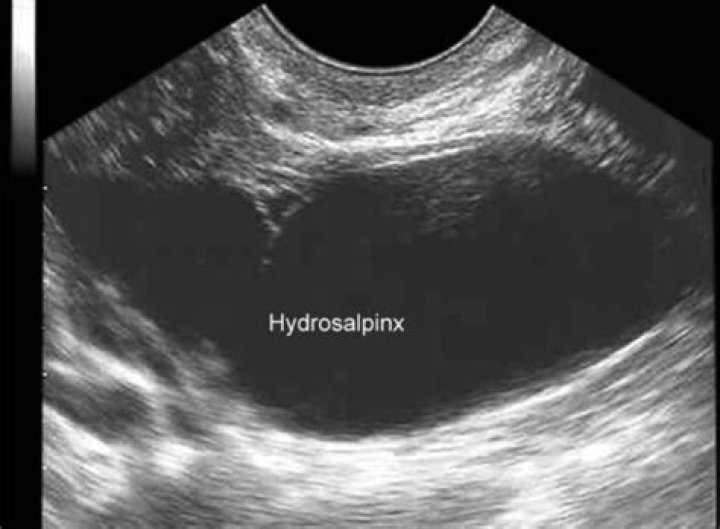

Can Hydrosalpinx be cancer

Hydrosalpinx in postmenopausal woman is rare. Most commonly it is due to primary ovarian malignancy with fallopian tube involvement or primary fallopian tube carcinoma. But hydrosalpinx with no malignancy in the fallopian tube, associated with synchronous malignancy of ovary and endometrium is rare.

Can you see hydrosalpinx on ultrasound?

Your doctor may be able to detect the presence of a hydrosalpinx on ultrasound. If your tube appears enlarged on ultrasound, this usually indicates a more severe hydrosalpinx. Your doctor will make a small opening in your belly and insert a special telescope or laparoscope to look at your uterus and fallopian tubes.